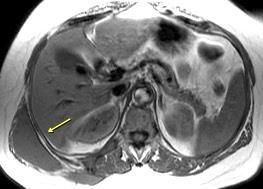

Tumor desmoide (“Fibromatosis agresiva”)

T1: Isointensos con músculos.

T2: Señal intermedia y de alta intensidad.

Presencia frecuente de áreas curvilíneas y lineales dentro de la lesión

Mansour J et al. Diagnostic and Imaging Approaches to Chest Wall Lesions. Radiographics 2022